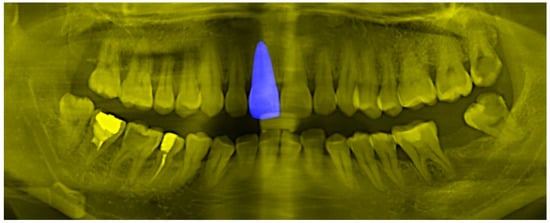

As mentioned in 3.3, high image information entropy will interfere with the DNN model, making the model learn many non-robust features. In 3.4, this paper implements a multi-channel tooth semantic structure information map, because in the image, most of the pixel values are binarized, so the information entropy of the image is low. In order to prove the advantages of the low information entropy image, this paper designs a tooth semantic structure map with high information entropy as the ablation experimental sample. The high information entropy also provides the DNN classification model with the global information of the teeth, the position information of the teeth and the shape information of the teeth. The specific construction method is relatively simple. The segmented image of the object instance of the tooth is inserted into the blue channel of the original tooth grayscale image, as shown in Figure 13. Theoretically, the image contains all the features in the tooth semantic structure information map proposed in 3.4, but the information entropy is higher than in the tooth semantic structure information map.

Figure 13.

In order to prove the effectiveness of the information entropy compression method, a high information entropy tooth semantic structure information map was constructed, which still includes the position and shape features of the teeth, and also includes the global tooth features.